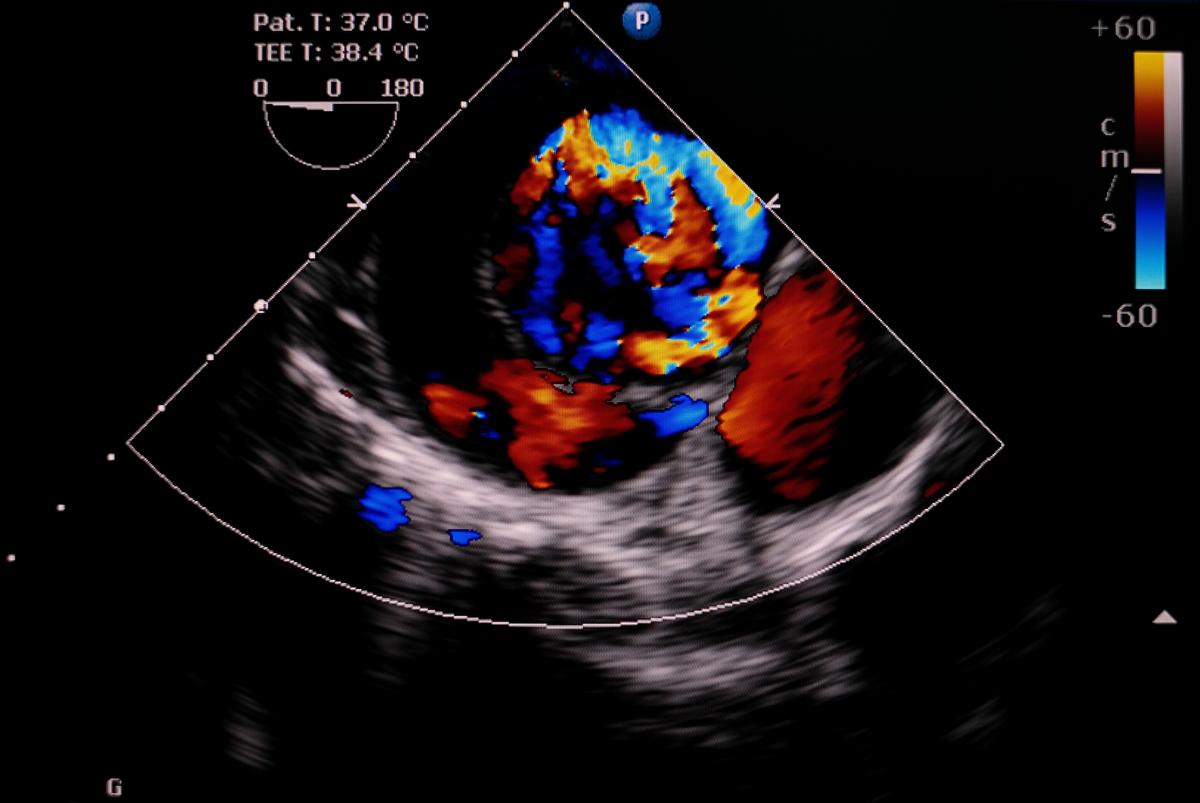

Echocardiography image of aortic dissection type A PIJITRA PHOMKHAM/Shutterstock

He rushed home, was hospitalized and underwent the appropriate diagnostics to determine the presence of an aortic aneurysm or widening of the aorta and then a discrete tear which blood flow now goes through the true lumen and a false lumen created by the dissection.  This occurs in the outer third of the media or the muscular layer of the blood tube.